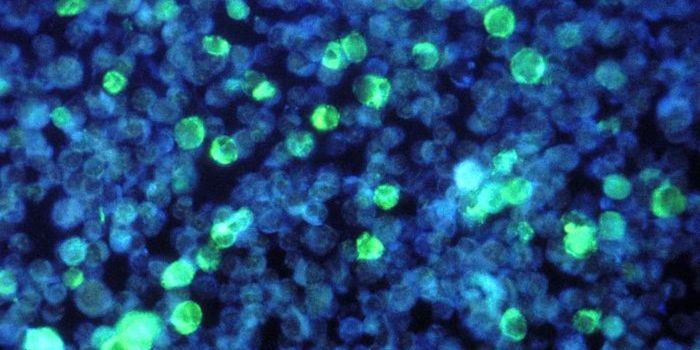

FEB 21, 2023Cell & Molecular BiologyThe Griffith Lab at UNC discovered telomeric protein & potential biomarker VR (green), shown in the nuclei (blue) of hum ...